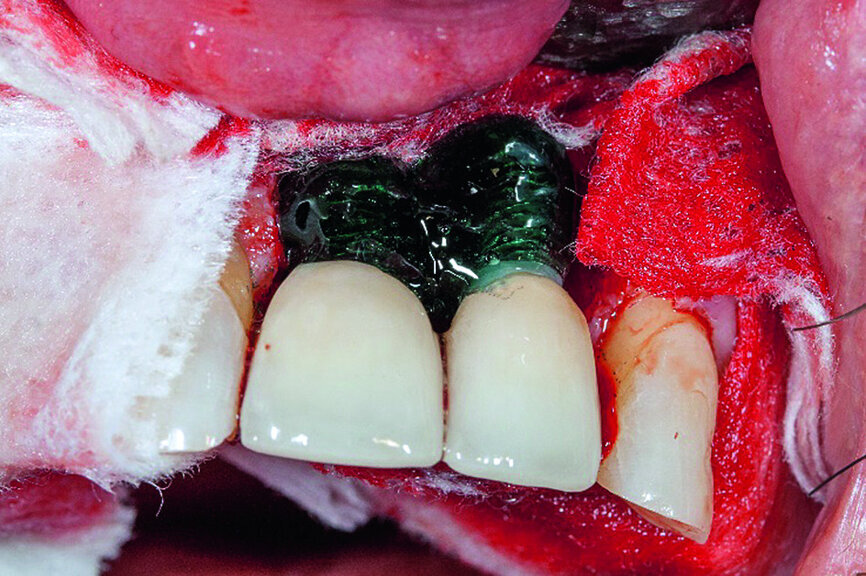

In accordance with the described protocol, a mucoperiosteal flap was created in order to obtain full access to the severe four-wall defect (Fig. 3). The implant surface was mechanically cleaned with diamond-coated burs (Fig. 4). Chemical debridement of the surface with subsequent antibiotic impregnation was performed (Figs. 5 & 6).

After completion of the preparatory steps, the bone replacement material consisting of phase-free beta-tricalcium phosphate—which offers optimal conditions for osseous remodelling owing to its micro-, meso- and macropores—was inserted as previously described (Fig. 7).